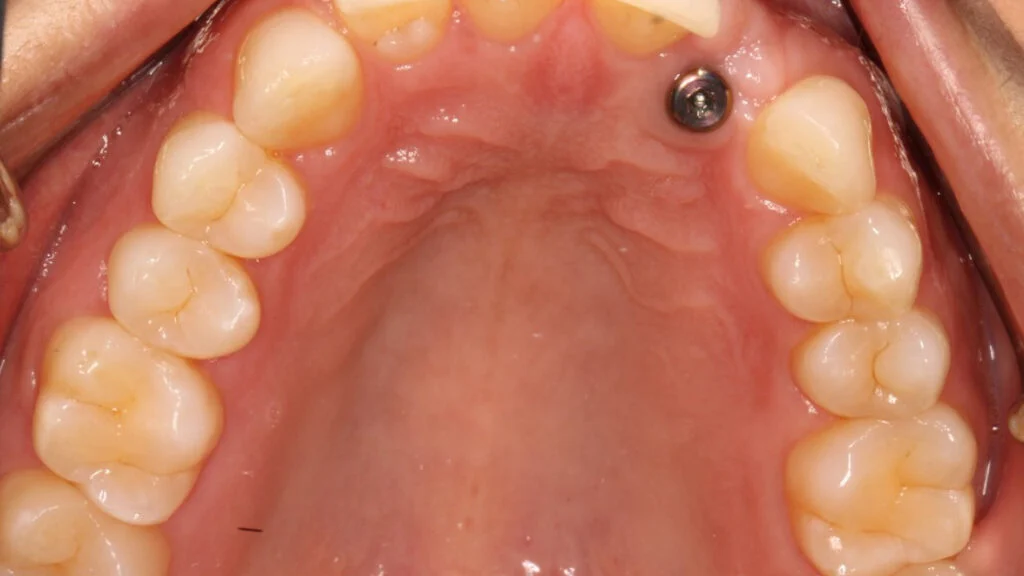

immediate loading vs delayed loading implants1 Immediate loading vs delayed loading implants

immediate loading vs delayed loading implants2 Immediate loading vs delayed loading implants

immediate loading vs delayed loading implants3 Immediate loading vs delayed loading implants

immediate loading vs delayed loading implants4 Immediate loading vs delayed loading implants